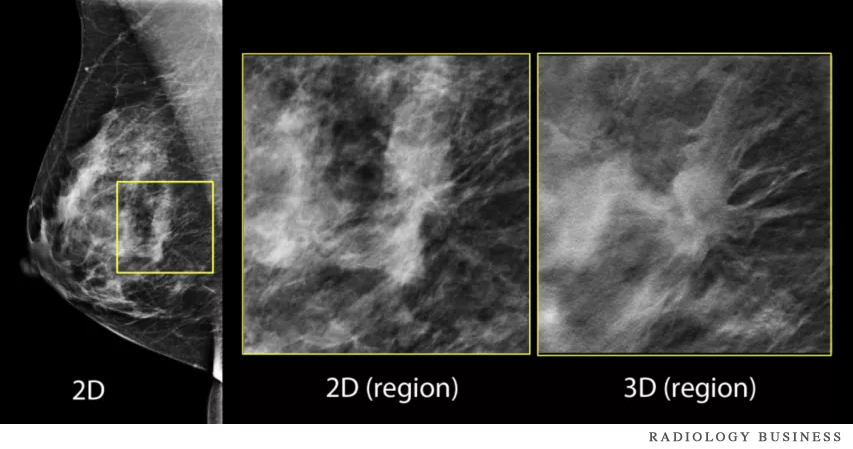

3D Mammography, also known as Digital Breast Tomosynthesis, works by capturing multiple images of the breast from several different angles. These images are then reconstructed into thin, layered slices, allowing radiologists to examine breast tissue in greater detail—almost like turning the pages of a book. This advanced imaging method minimizes the chance that overlapping tissue will hide potential issues, improving both detection rates and diagnostic confidence.

C-View Technology

• Clearer, more detailed images of dense breast tissue